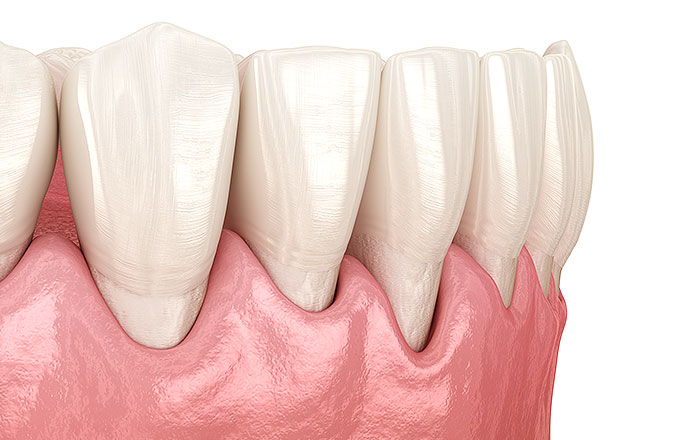

歯茎の変化

年齢とともに歯茎が痩せて下がり、歯の根元が見えてくることがあります。これを歯肉退縮(しにくたいしゅく)といい、鏡を見たときに「歯が長くなった気がする」と感じる原因の一つです。

歯肉退縮が起こると、見た目の変化だけでなく、冷たいものや熱いものがしみる知覚過敏の症状が出やすくなります。これは、エナメル質に守られていない歯の根元部分が露出し、刺激を受けやすくなるためです。